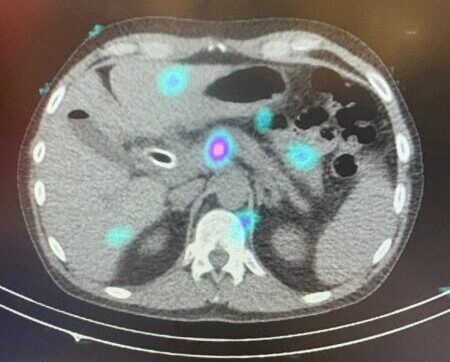

Primeiro tratamento com o dispositivo OncoSil™ realizado em Portugal

Um marco histórico na luta contra o cancro do pâncreas, em colaboração com o IPO-Porto…